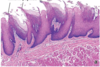

Nasal Vestible

Keratinized stratiefied squamous epithelium

Masticatory mucosa of the oral cavity

note the parakeratinized and keratinized stratified squamous epithelium

Masticatory mucosa

bone (lower left) and lamina propria

Lining mucosa

nonkeratinized stratified squamous